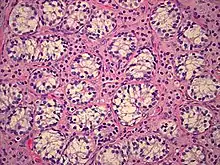

The gonads in these women are not ovaries, but instead, are testes; during the embryonic stage of development, testes form in an androgen-independent process that occurs due to the influence of the SRY gene on the Y chromosome.[26][27] They may be located intra-abdominally, at the internal inguinal ring, or may herniate into the labia majora, often leading to the discovery of the condition.[1][28][29][30] Testes in affected women have been found to be atrophic upon gonadectomy.[31]

- Hannema SE, Scott IS, Rajpert-De Meyts E, Skakkebaek NE, Coleman N, Hughes IA (March 2006). "Testicular development in the complete androgen insensitivity syndrome". J. Pathol. 208 (4): 518–27. doi:10.1002/path.1890. PMID 16400621. S2CID 20730666.